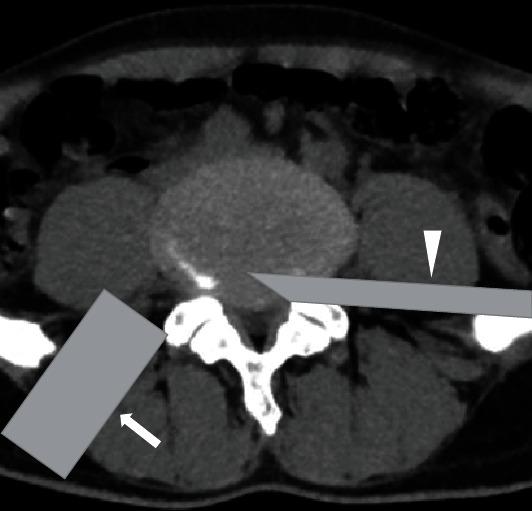

The purpose of this study was to investigate the feasibility and clinical efficacy of the percutaneous bilateral endoscopy technique (microendoscopic trans-Kambin's triangle lumbar interbody fusion + percutaneous endoscopic transforaminal decompression of the lumbar spinal canal, ME-TKT-LIF+ PETD) in the treatment of lumbar degenerative diseases.

From May 2016 to September 2018, 29 patients (16 males and 13 females) who suffered from neurologic symptoms due to degenerative lumbar spine disease and underwent percutaneous bilateral endoscopy technique were enrolled. A microendoscope was used for fusion, and a percutaneous endoscope was used for spinal canal decompression. These patients' perioperative and clinical outcome-related parameters were collected and analyzed.